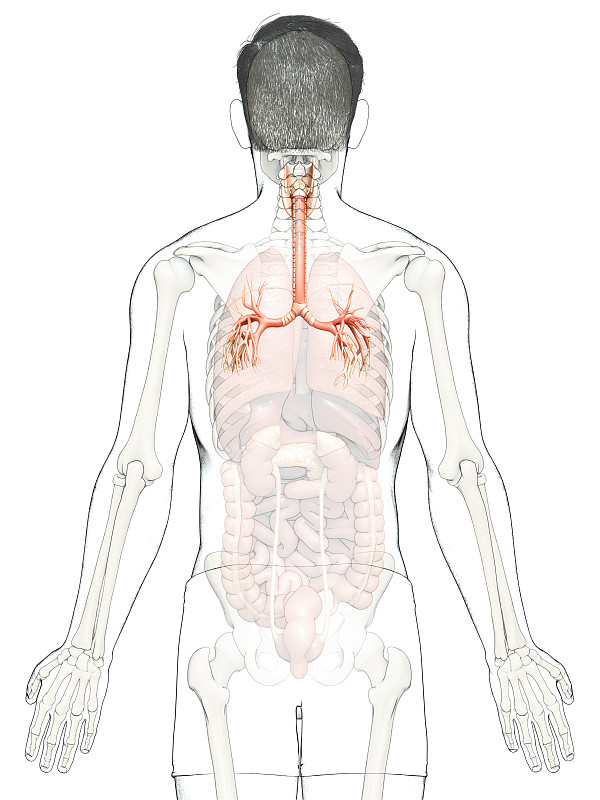

人体呼吸系统肺解剖学详情

JPG

人体呼吸系统肺解剖学详情

JPG

人体呼吸系统肺解剖学详情

JPG

人体呼吸系统肺解剖详情

JPG

人体呼吸系统肺解剖详情

JPG

人体呼吸系统肺解剖学详情

JPG

人体呼吸系统肺解剖学详情

JPG

人体呼吸系统肺解剖学详情

JPG

人体呼吸系统肺解剖学详情

JPG

人体呼吸系统肺解剖学详情

JPG

人体呼吸系统肺解剖详情

JPG

人体呼吸系统肺解剖学详情

JPG

人体呼吸系统肺解剖学详情

JPG

人体呼吸系统肺解剖详情

JPG

人体呼吸系统肺解剖详情

JPG

人体呼吸系统肺解剖学详情

JPG